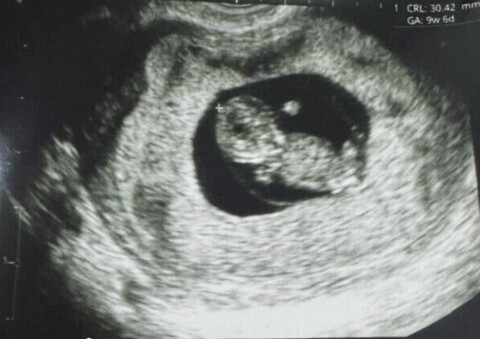

Американская биотехнологическая компания Gameto, возглавляемая женщинами, объявила о первом в мире живорождении с использованием процедуры Fertilo, при которой яйцеклетки созревают вне тела женщины. Компанией руководит Дина Раденкович — женщина-врач, ставшая предпринимательницей. 16 декабря компания предоставила пресс-релиз, в котором рассказывается об успехе новой технологии Fertilo.

Технология Fertilo сокращает время гормональной стимуляции до 2-3 дней. Сначала женщина проходит через трехдневную стимуляцию невысокими дозами гонадотропина. Затем незрелые яйцеклетки помещают в генноинженерную культуру поддерживающих клеток, которая имитирует молодую ткань яичника, реагирующую на гормоны и самостоятельно их вырабатывающую.